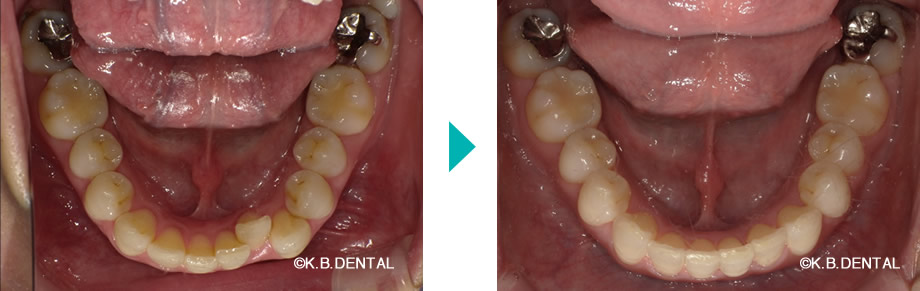

上下前歯部の叢生が著しい症例

| 主訴 | 歯並びが気になる |

|---|---|

| 診断名 | 叢生 |

| 初診時年齢/性別 | 40代男性 |

| 装置 | マウスピース矯正(インビザラインGo) |

| 抜歯/非抜歯 | 非抜歯 |

| 治療期間 | 約1年半 |

| 費用 | 約70万円(税別) |

| リスク副作用等 | 矯正歯科治療のリスク副作用について |